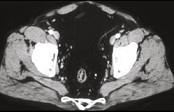

问题 男,41岁,腹痛、腹泻、腹胀、脓血便、里急后重、疲乏无力,结合图像,选择最可诊断 ( )

选项 A.溃疡性结肠炎 B.结肠克罗恩病 C.结肠结核 D.假膜性肠炎 E.结肠淋巴瘤

答案 A